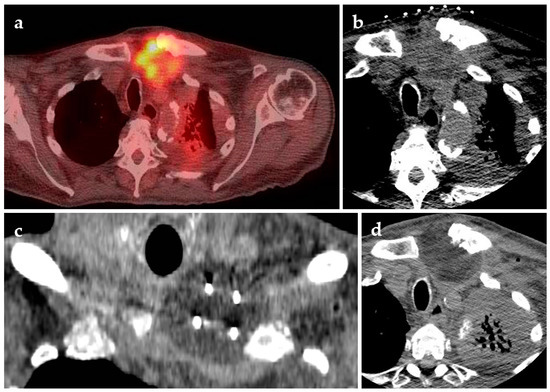

- Chheang, S.; Abtin, F.; Guteirrez, A.; Genshaft, S.; Suh, R. Imaging features following thermal ablation of lung malignancies. Semin. Intervent. Radiol. 2013, 30, 157–168. [Google Scholar] [CrossRef] [PubMed]